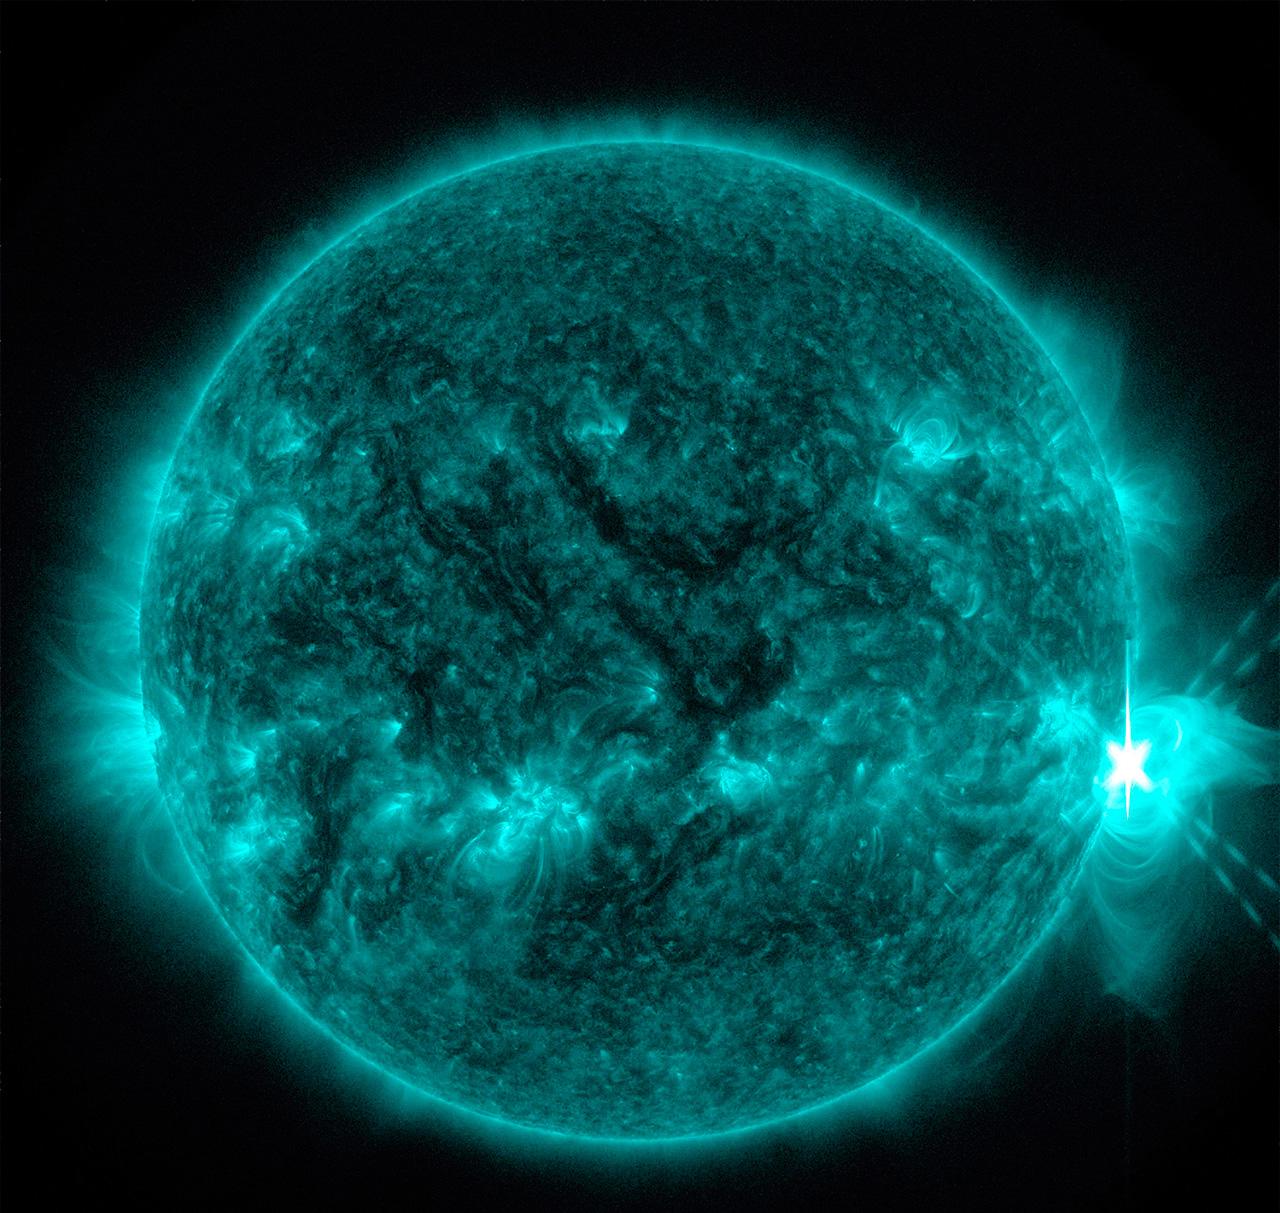

อันดับหนึ่ง ภาพถ่ายเกี่ยวกับภาพถ่ายเอกซเรย์ ที่ถูกรวบรวมและจัดทำโดยเว็บไซต์ cleverlearn-hocthongminh.edu.vn นอกจากนี้ยังมีภาพถ่ายที่เกี่ยวข้องกับ บริษัท อีเอ็กซ์พี ซิสเต็ม จํากัด, เสีย ภาษี 1 เปอร์เซ็นต์, หักภาษี ณ ที่จ่าย กี่เปอร์เซ็นต์, ทริปเปิ้ลเอ๊กซ์ 2 พยัคฆ์ร้ายพันธุ์ดุ 2005, ภาษี 7 เปอร์เซ็นต์ คือ, หักภาษี ณ ที่จ่าย 3 เปอร์เซ็นต์ ดูรายละเอียดด้านล่างค่ะ

ภาพถ่ายเอกซเรย์

ขอบคุณที่ต้องการเสริมสร้างความรู้ด้วยการอ่านบทความ ภาพถ่ายเอกซเรย์ ที่มีให้บริการที่ cleverlearn-hocthongminh.edu.vn ค่ะ ท่านสามารถแสดงความคิดเห็นและตรวจสอบบทความที่เกี่ยวข้องเพิ่มเติมที่ด้านล่างค่ะ หวังว่าจะเป็นประโยชน์ในการให้ข้อมูลที่น่าสนใจให้กับท่านค่ะ

Posts: ภาพถ่ายเอกซเรย์